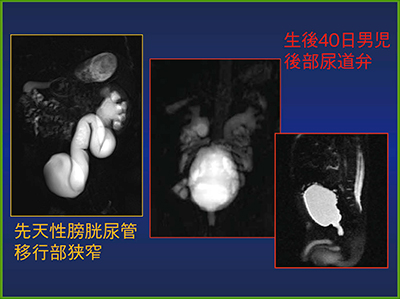

尿管疾患に対するMRU

尿管疾患では排泄性尿路造影に代わって,CTUが第一選択となりつつある。MRUは空間分解能がCTより劣ることや,尿路結石の診断が難しいことなどの理由から,適応は限定的とされるが,尿路造影剤が使えない場合や,被ばくを避けたい場合,特に小児などには有用である(図4)。

またMRUは,T2強調画像を利用して造影剤を使用しない方法と,T1強調画像を利用して少量の造影剤を使う方法とがある。前者では囊胞も消化管液も白くなり,尿路描出が不良となることがある。後者で脂肪抑制をかけると,CTUのように尿路が明瞭に確認できる。

図4 新生児の先天性膀胱尿管移行部狭窄のMRU